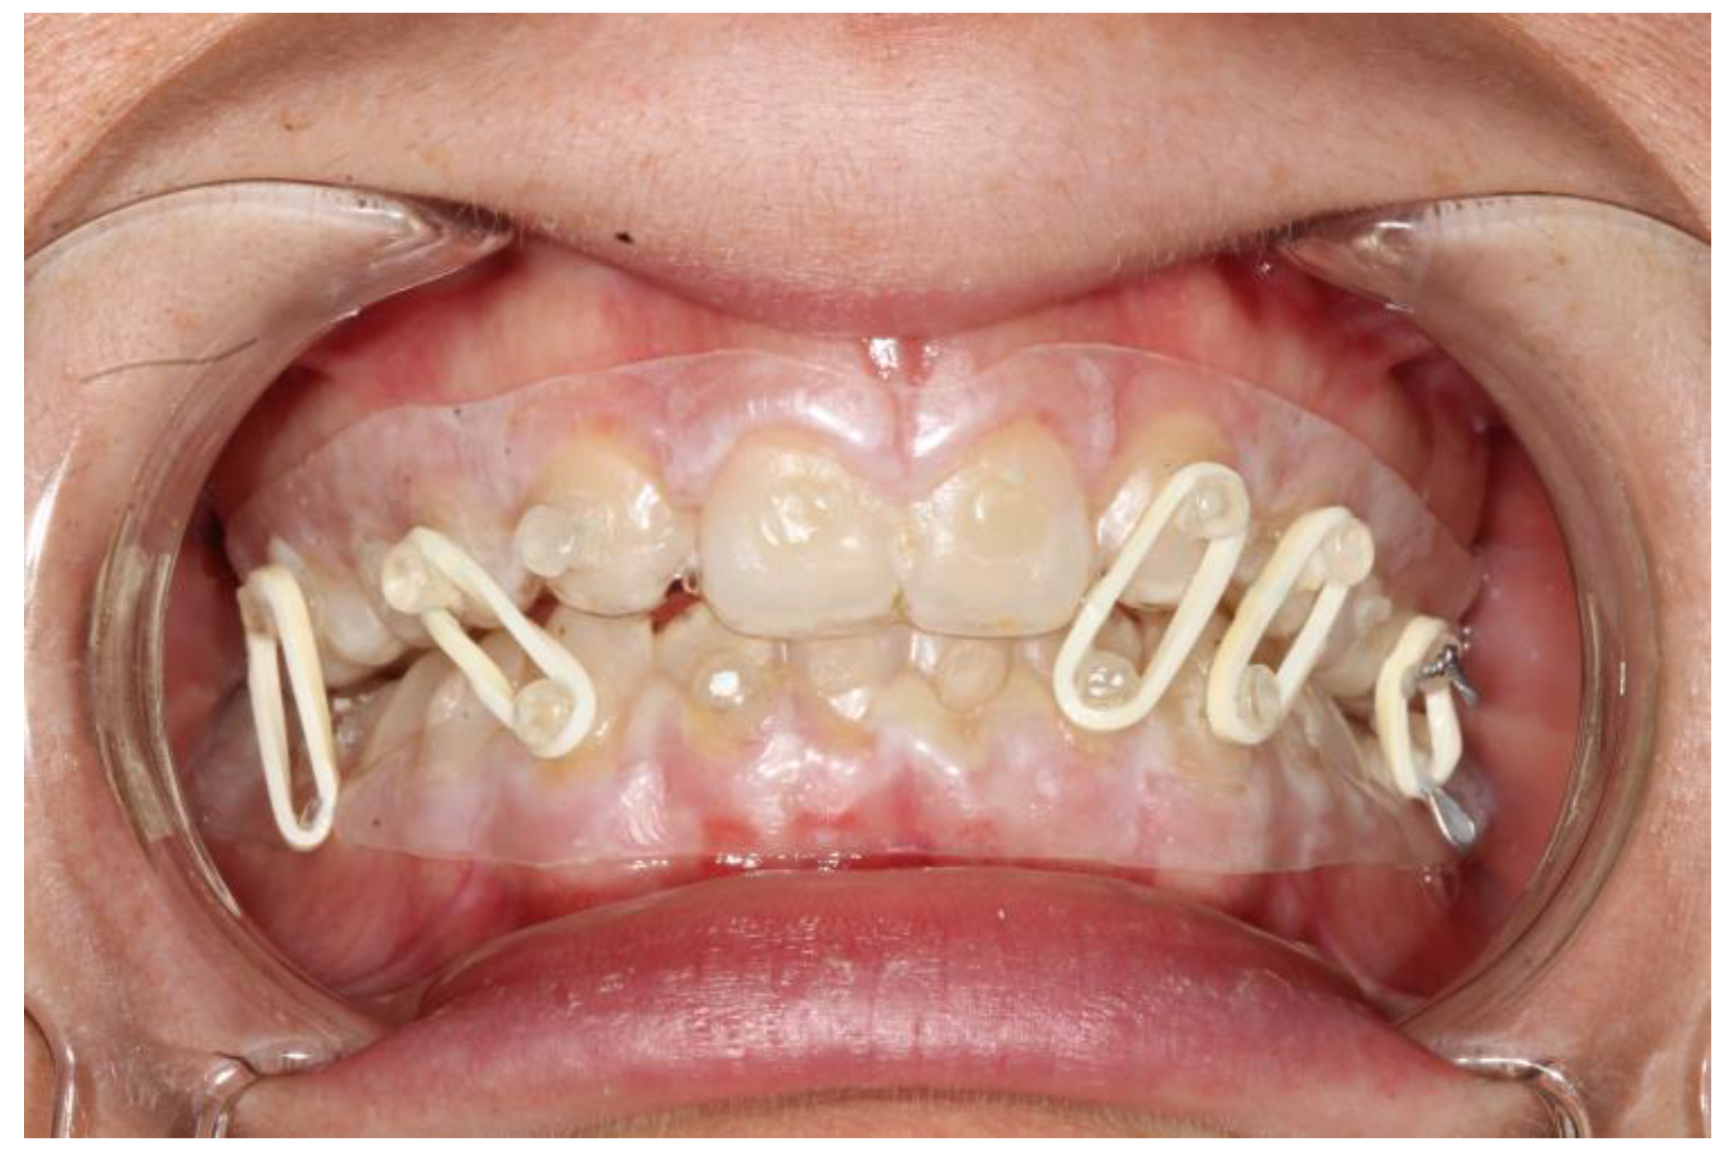

The splints were bonded to the teeth with a restorative flowable composite (Filtek Supreme Flowable, 3M, St. Paul, MN, USA), which was applied through the holes designed on the splint (Figure 1 and Figure 2).

The fixation strength of the intermaxillary fixation was considered adequate in both cases (Figure 5 and Figure 6).

Figure 1. Intraoral view of patient 2. It is possible to see the coronal fracture of element 4.2; the fitting of the splints is adequate and so is the fixation.